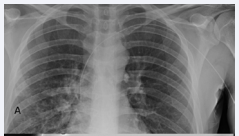

A 29 year male with chronic granulomatous disease had a left arm PICC (Vaxcel PASV, 4 fr single lumen polyurethrane, Navilyst, Marlborough, Mass) line placed for antibiotic therapy to treat a lung infection (Figure 1A).

Figure 1: A, B: During attempted removal after 7 weeks of antibiotic therapy, PICC line was withdrawn from central position (A) but could not be removed beyond upper left brachial vein (arrow, B). C-Case 1: Twelve hours after instillation of tPA, PICC line could be easily removed along with section of fibrin sheath still adherent to distal third of catheter.

Seven weeks after successful completion of therapy, during attempted removal, the PICC line became stuck after half (27cm) of the catheter had been withdrawn (Figure 1B). Rather than trying additional forced traction, we slowly injected 2mg of r- tPA diluted with normal saline to a volume of 5ml over 1 minute through the lumen of the PICC line while maintaining gentle traction on the catheter. The r-tPA was allowed to dwell overnight, and the patient was instructed to return the following morning. Under fluoroscopic visualization the PICC line was removed with gentle traction along with a fibrin sheath/thrombus still adherent to distal third of catheter (Figure 1C).